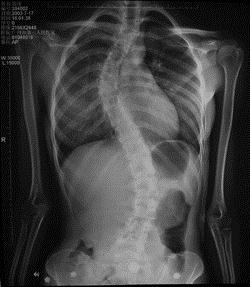

病历摘要: 患者××,女,17岁,发现剃刀背畸形3个月。查体:脊柱胸段向右侧凸,腰段向左侧凸,右胸廓呈剃刀背畸形,双下肢未见明显异常。该患者的手术...

问题 病历摘要: 患者××,女,17岁,发现剃刀背畸形3个月。查体:脊柱胸段向右侧凸,腰段向左侧凸,右胸廓呈剃刀背畸形,双下肢未见明显异常。 该患者的手术方案:

选项 A、胸段用挂钩、腰段打椎弓根钉系统+植骨融合 B、前路微创手术 C、后路矫正 D、后路全椎弓根钉内固定系统矫正+植骨融合 E、前路矫正

答案 CD